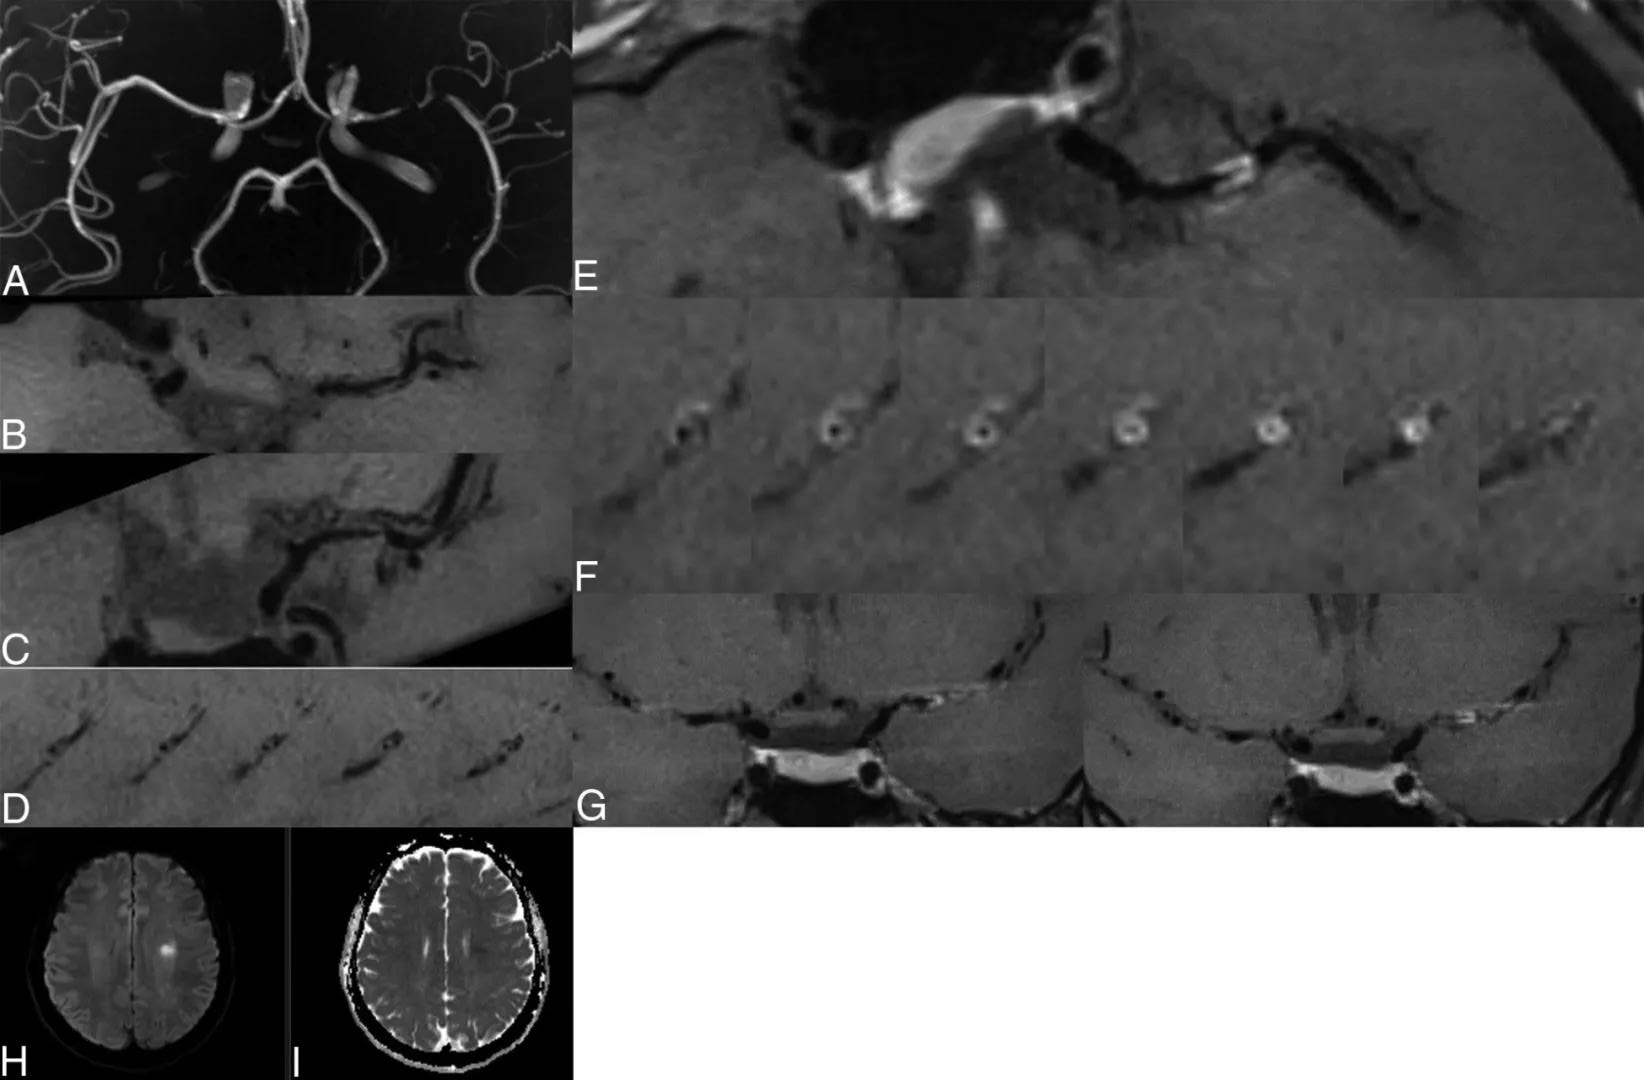

图2. 37岁,男性。3D TOF-MRA MIP图像显示左MCA狭窄(A)。HR-VW-MR成像,左侧 MCA 狭窄部位的强化前 T1影像显示等信号病变,表面不规则(B和C)。斜矢状位图像显示血管壁同心增厚病变,累及环形壁(D)。增强后T1图像显示病变呈强烈(II级)同心强化(E-G)。DWI显示左半卵圆心有一个小的斑片状急性缺血性病变,弥散抑制(H和I)